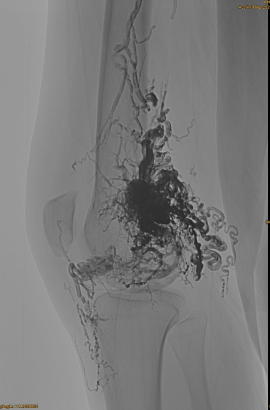

患者の基本情報:女性、36歳。 AVM骨盤、股関節、膝、左osg、複数のpre -塞栓術。

使用される製品:3PCS LAVA-34,14PCS LAVA-18。

最終結果:

静脈流出はほとんどありません:

後期、別のEMBOが必要ですが、はるかに優れています: